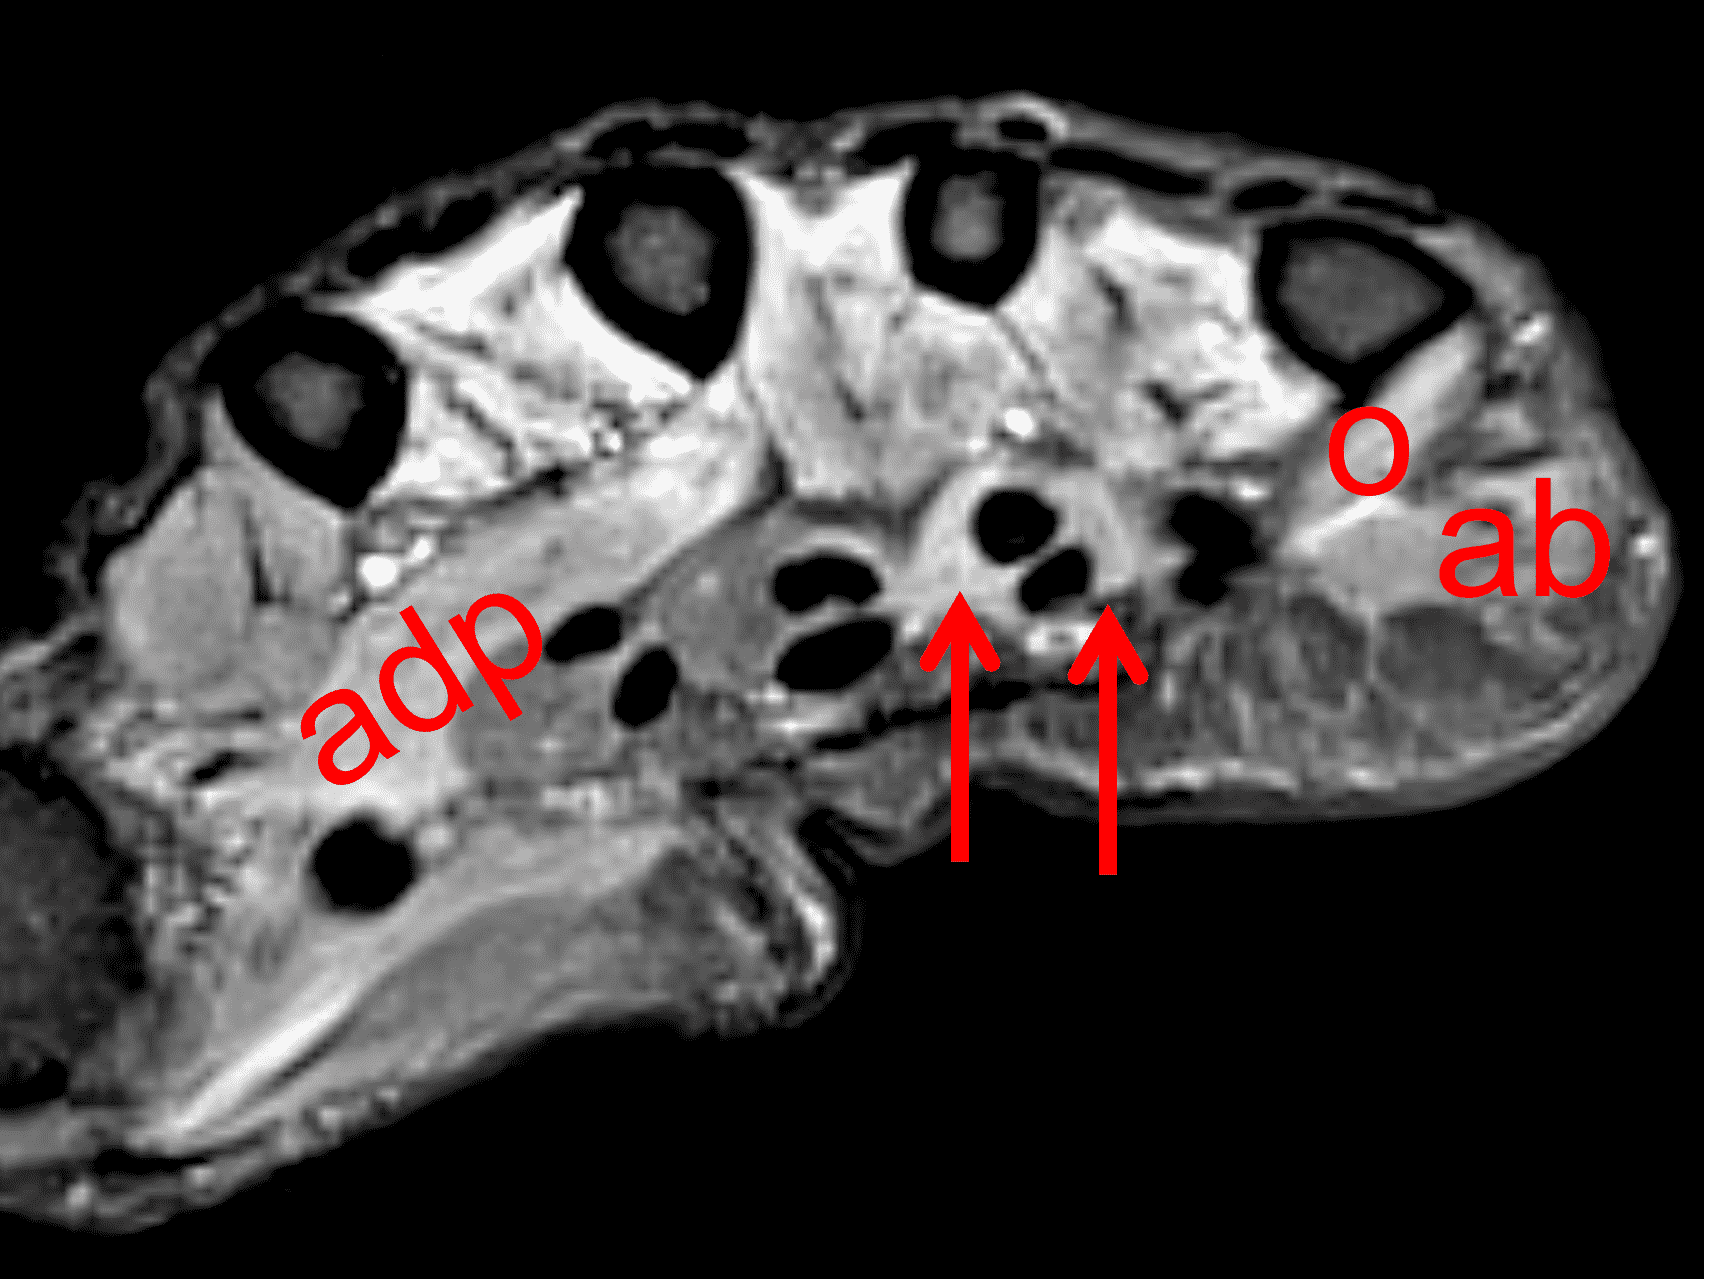

Figure 16: Ulnar neuritis with muscle denervation. In addition to sensory symptoms, this woman also presented with decreased grip strength. (16A) Axial STIR image through the proximal palm shows high signal intensity within the dorsal (d) and palmar (p) interosseous muscles, representing subacute denervation in the ulnar nerve distribution. (16B) A STIR image slightly more distally also shows subacute denervation involving the adductor pollicis (adp), opponens digiti minimi (o), abductor digiti minimi (ab), and third and fourth lumbrical (arrows) muscles. Despite having no symptoms at the elbow, nerve conduction studies and EMG confirmed ulnar nerve dysfunction at the cubital tunnel.